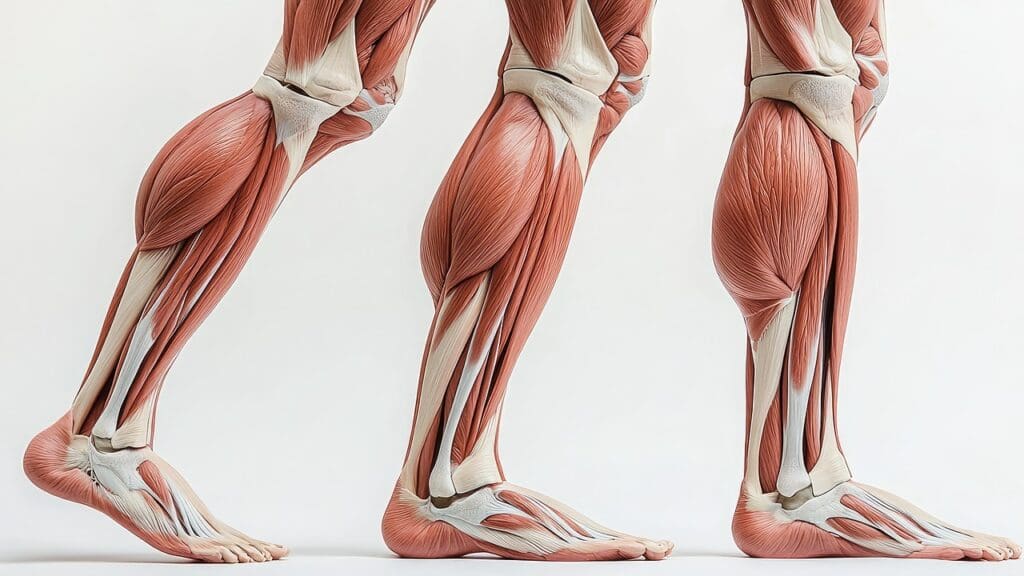

Anatomy of the Posterior Leg

The back of the leg, or posterior leg, has muscles, tendons, and nerves. The main muscles are the gastrocnemius and soleus, forming the calf muscles. These muscles are key for ankle movement and stability. Knowing the anatomy helps pinpoint the pain’s source.